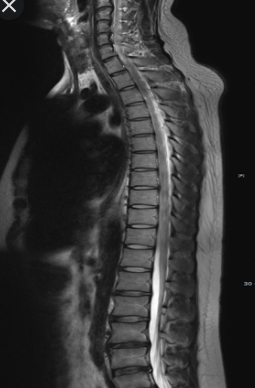

2018년 10월에 뇌 MRI 보험적용이 바뀌게 됩니다. 2018년 10월 이전에는 중증 뇌질환환자로 의사가 인정하는 경우에만 제한적으로 건강보험 적용이 되었습니다. 해당 상병으로는 뇌출혈, 외전증, 뇌경색 등이 있습니다.

하지만 2018년 10월에는 뇌혈관 및 뇌 MRI 가 건강보험 적용이 확대 되었습니다. 경증인 뇌질환이나 신경학적으로 이상이 있거나, 검사상 이상소견이 있다면 건강보험이 적용이 가능해졌습니다.

그리고 뇌질환이 의심되는 두통이 있거나, 어지러움이 있고 신경학적 검사를 실시한 경우에도 건강보험이 적용이 되어서 많은 국민들의 부담이 줄어들었습니다.

하지만 재정악화 및 무분별한 MRI 시행으로 또 제도가 바꼈습니다. 2020년 4월 1일에 개선안이 나왔는데요.

신경학적 검사상 이상 증상 또는 뇌혈관 질환이 강력하게 의심되는 경우에만 건강보험이 적용되는걸로 바꼈습니다.

그리고 뇌질환이 의심되는 두통, 어지로움으로 MRI 검사를 받았다면 본임부담이 80%로 바꼇습니다. 그렇기 때문에 의사의 판단하에 따라 금액이 많이 차이가 나게 되었습니다.

보통 MRI 보험적용은 의사의 진료하에 따라 확인이 가능하게됩니다. 이상소견이 없다면 비급여로 처리되기 때문에 금액이 최소 50~100만원 정도 금액이 청구됩니다.